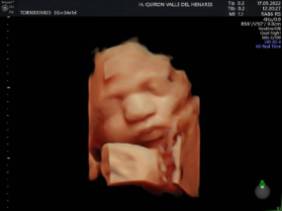

El Hospital Quirónsalud Valle del Henares incorpora un nuevo ecógrafo con tecnología 5 D

El Hospital Quirónsalud Valle del Henares ofrece la posibilidad de realizar ecografías gestacionales 5D. Este tipo de exploración permite obtener una imagen muy realista del bebé y se puede realizar en cualquier etapa de la gestación -aunque lo recomendado es realizarla entre las semanas 28 y 32 de gestación, ya que técnicamente es el mejor momento y es mucho más probable obtener imágenes de buena calidad-.

Al final de la prueba, se entrega a la familia un informe de la ecografía y un soporte digital que contiene las imágenes y los vídeos realizados. Las ecografías 4D y 5D son también llamadas emocionales por la explosión de sensaciones que genera cuando la madre ve por primera vez la imagen del bebé que espera.

"Realizar esta ecografía con nuestro equipo de diagnóstico prenatal tiene un valor añadido -señala la Dra. Rocío Vellido Cotelo, Jefa Asociada de Ginecología y Obstetricia del Hospital Quirónsalud Valle del Henares, dado que quien realiza la prueba es un especialista en la materia, siempre se completa la exploración con un examen morfológico y de perfil biofísico fetal, que permita valorar el estado de bienestar del bebé más allá de la captura de videos y fotografías".